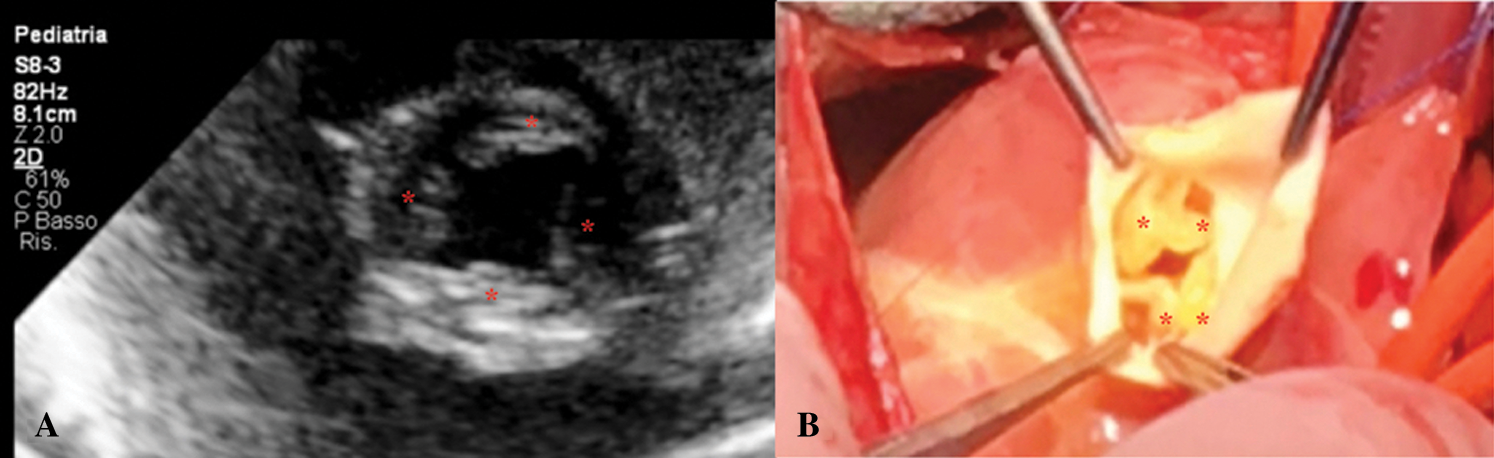

Echocardiogram showed CAT Type II CE (Fig. 1), a quadricuspid truncal valve (Figs. 2A and 2B) with moderate stenosis (Gmax 40 mmHg), reversal flow in descending aorta due to significant truncal valve regurgitation, and ventricular septal defect of 8 mm shunting left-to-right. Single coronary ostium was detected at 10 o’ clock in short axis view.

Figure 2: A. Short-axis view of quadricuspid (asterisk) common arterial trunk valve. B. Surgical view of quadricuspid (asterisk) common arterial trunk valve